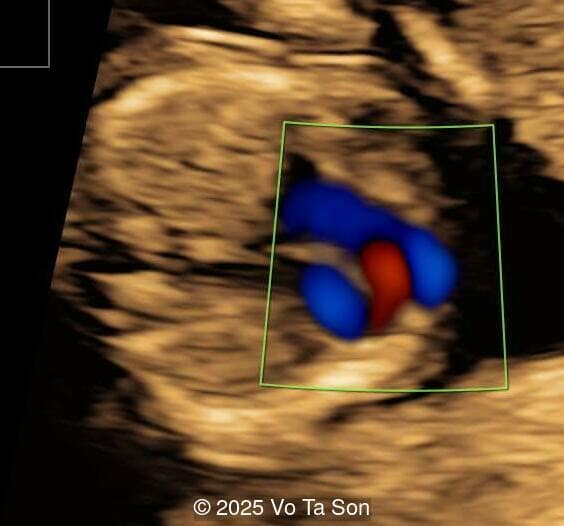

- Ventricular septal defect (VSD)

- Tricuspid valve regurgitation

- Right aortic arch